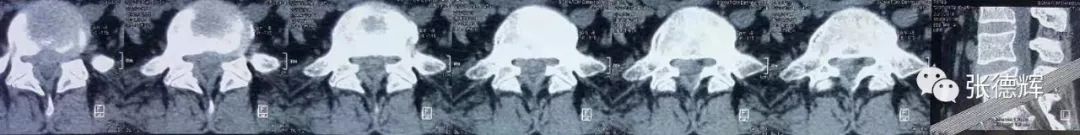

患者术前的各项影像检查

腰椎正侧位X光片及动力位片未见明显骨质结构异常及腰椎失稳

腰椎核磁及CT均提示腰5-骶1巨大椎间盘脱出,椎管占位,马尾神经受压明显

根据患者的这些临床症状及其影像学检查结果

我们判断—— 患者为“ 腰5骶1巨大椎间盘脱出 ”并有“ 马尾综合征 ”迹象